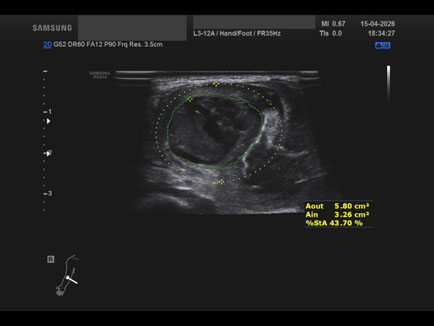

Data inserimento: 17/04/2026

Ecografia del: 15/04/2026

Strumento: Samsung

Sonda: Lineare

Commento all'esame: ematoma post trauma da sforzo del lungo supinatore dx in anziano sottoposto a terapia con i NAO.

Conclusioni: ematoma del muscolo lungo supinatore destro (hematoma of the right supinator longus muscle).

Realizzazione: Dr. F. Pietro Tarini - Gubbio (PG)